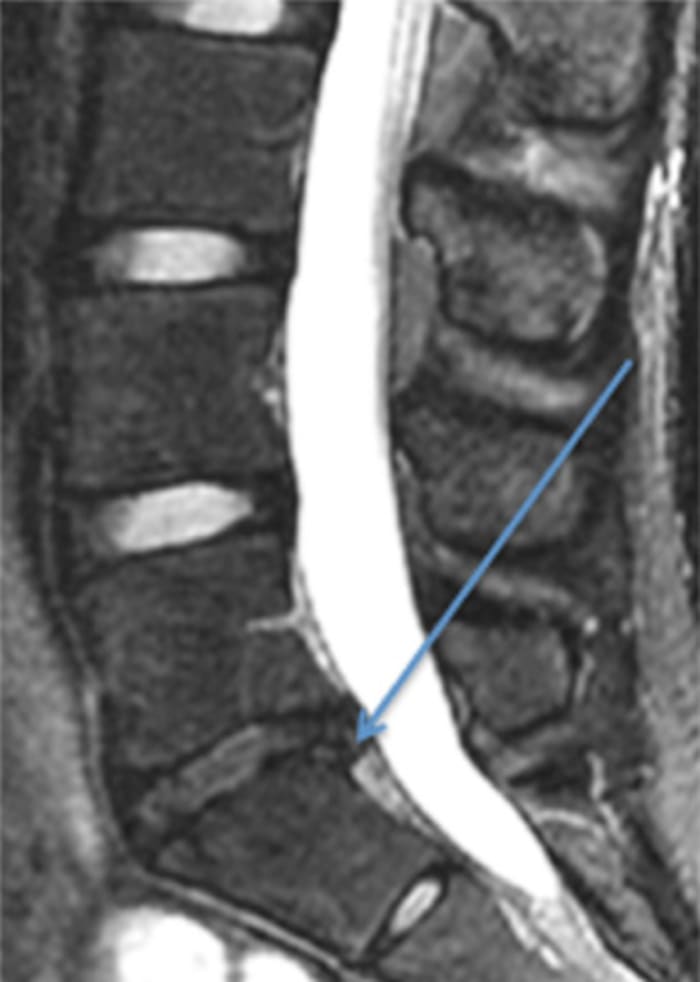

Another common injury to the low back of athletes is a herniated intervertebral disc. Professional athletes such as Tony Romo, Dwight Howard and Marian Hossa have all suffered this injury. The intervertebral discs are shock absorbers between the bones in the back. They are composed of a gel-like center portion (the nucleus pulposus) surrounded by a firm fibrous outer layer (the annulus fibrosis). If there is an injury to the outer fibrous layer, the inner portion can extrude out and compress local nerve roots (Figure 2). This often presents with pain shooting down a patient’s leg, and it may be associated with significant numbness, tingling and weakness in the leg.

Faced with these symptoms, athletes should immediately stop athletic activity and see a medical professional. Fortunately, these symptoms will often resolve in four to six weeks with rest and anti-inflammatory medications. However, if symptoms persist, surgical intervention can lead to a significant improvement in symptoms for most patients. Furthermore, surgical treatment for a herniated disc does not preclude patients from returning to sports, as over 80% of athletes who develop a herniated intervertebraldisc can return to sporting activity.

Like stress fractures, there is no way to totally prevent a herniated intervertebraldisc. One of the major risk factors for developing a herniated disc is a family history of a herniated disc; additionally athletes who participate in sports that require substantial axial loading or flexion/rotation through the lumbar spine, such as football, weightlifting and bowling, may be at an increased risk. It is critical to maintain proper technique. Patients with a family history of herniated disc, or patients who are participating in one of these sports should be aware of the symptoms of a herniated disc, and seek medical attention immediately if they develop those symptoms.